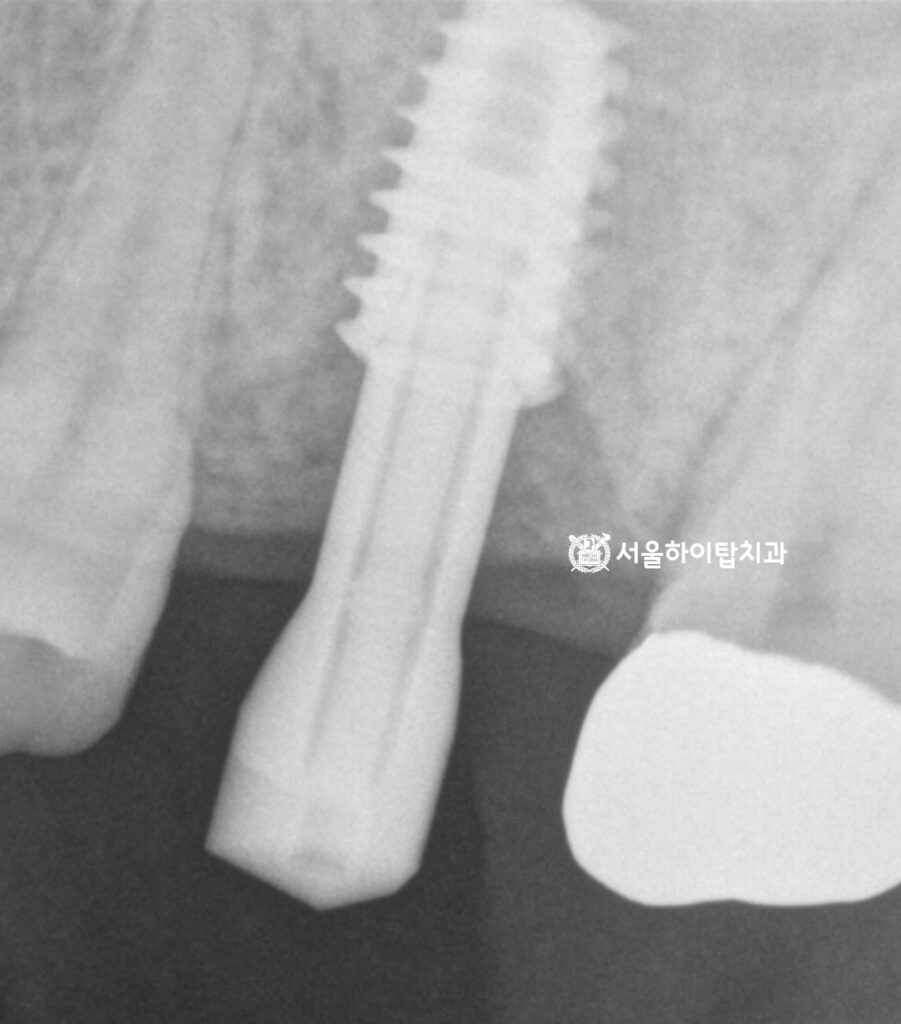

최종 보철을 위한 스캔바디 체결

골유착이 충분히 이루어지면, 이제 스캔바디를 체결하여

임플란트의 정확한 위치와 각도 정보를 디지털로 채득하게 됩니다.

스캔바디는 최종 보철을 제작하기 위한 기준이 되는 장치로,

이를 통해 구강 스캐너가 픽스처의 3차원적 위치를 정밀하게 기록할 수 있습니다.

이데이터로 치아 모양, 교합 관계, 주변 치아와의 조화를 고려한

맞춤형 지르코니아 크라운 제작으로 이어지게 됩니다.